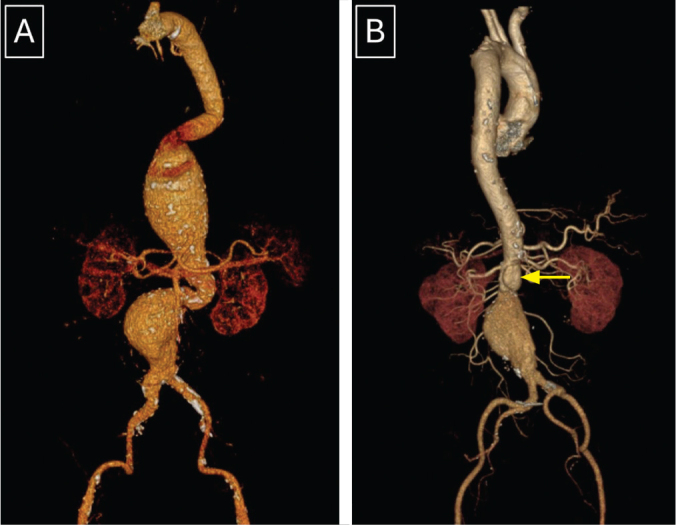

Repair of complex aortic aneurysms such as those involving the thoracoabdominal and pararenal aorta presents a formidable challenge for surgeons with significant perioperative morbidity and mortality. A hybrid procedure combining renovisceral debranching with endovascular aneurysm exclusion has been developed as an alternative approach for high-risk patients. This paper reports our initial experience with hybrid repair for these complex aortic diseases in three high-risk patients.